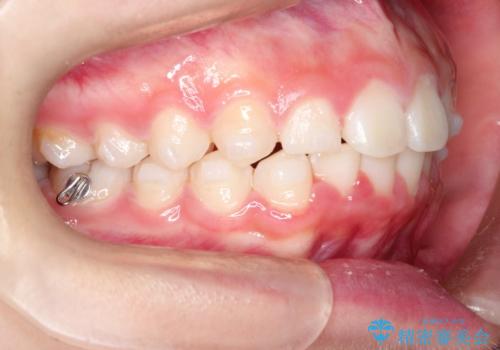

【インビザライン】出っ歯を引っ込めたい。

- 前歯の隙間と、出っ歯に見えることを主訴に来院されました。

できるだけ目立たない装置をご希望されましたので、インビザラインにて治療を行いました。

治療中は、できるだけ前歯を下げることができるように”顎間ゴム”を使用します。

”顎間ゴム”を利用することで、奥歯を後ろに動かす力を強めることができます。